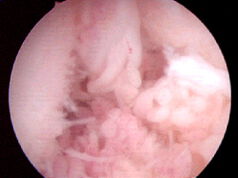

Freie Gelenkkörper:

Ausgesprengte größere Knorpel- bzw. -Meniskusanteile können zu freien Gelenkkörpern werden und Blockierungen im Gelenk verursachen. Zur Vermeidung von weiteren Schäden durch die Einklemmungen müssen diese entfernt werden.